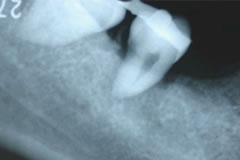

歯牙移植術の実際⑤  移植直後のデンタルX 線写真。

術後軟組織が安定する移植 4週間後に抜髄を行わなければなりません。また歯牙の固定は通常6週間行います。